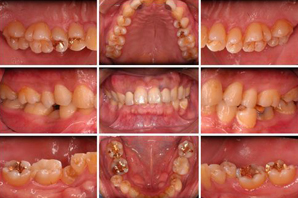

現在のお口の中の状態を、写真に撮り記録します。日常では、ご自身のお口の中の裏側や側面を見ることが困難ですので、検査結果ご報告の際には、PCを通じて説明いたします。聞いたり、鏡で見てもよくわからないのが写真を見てもらったらよくわかると思います。